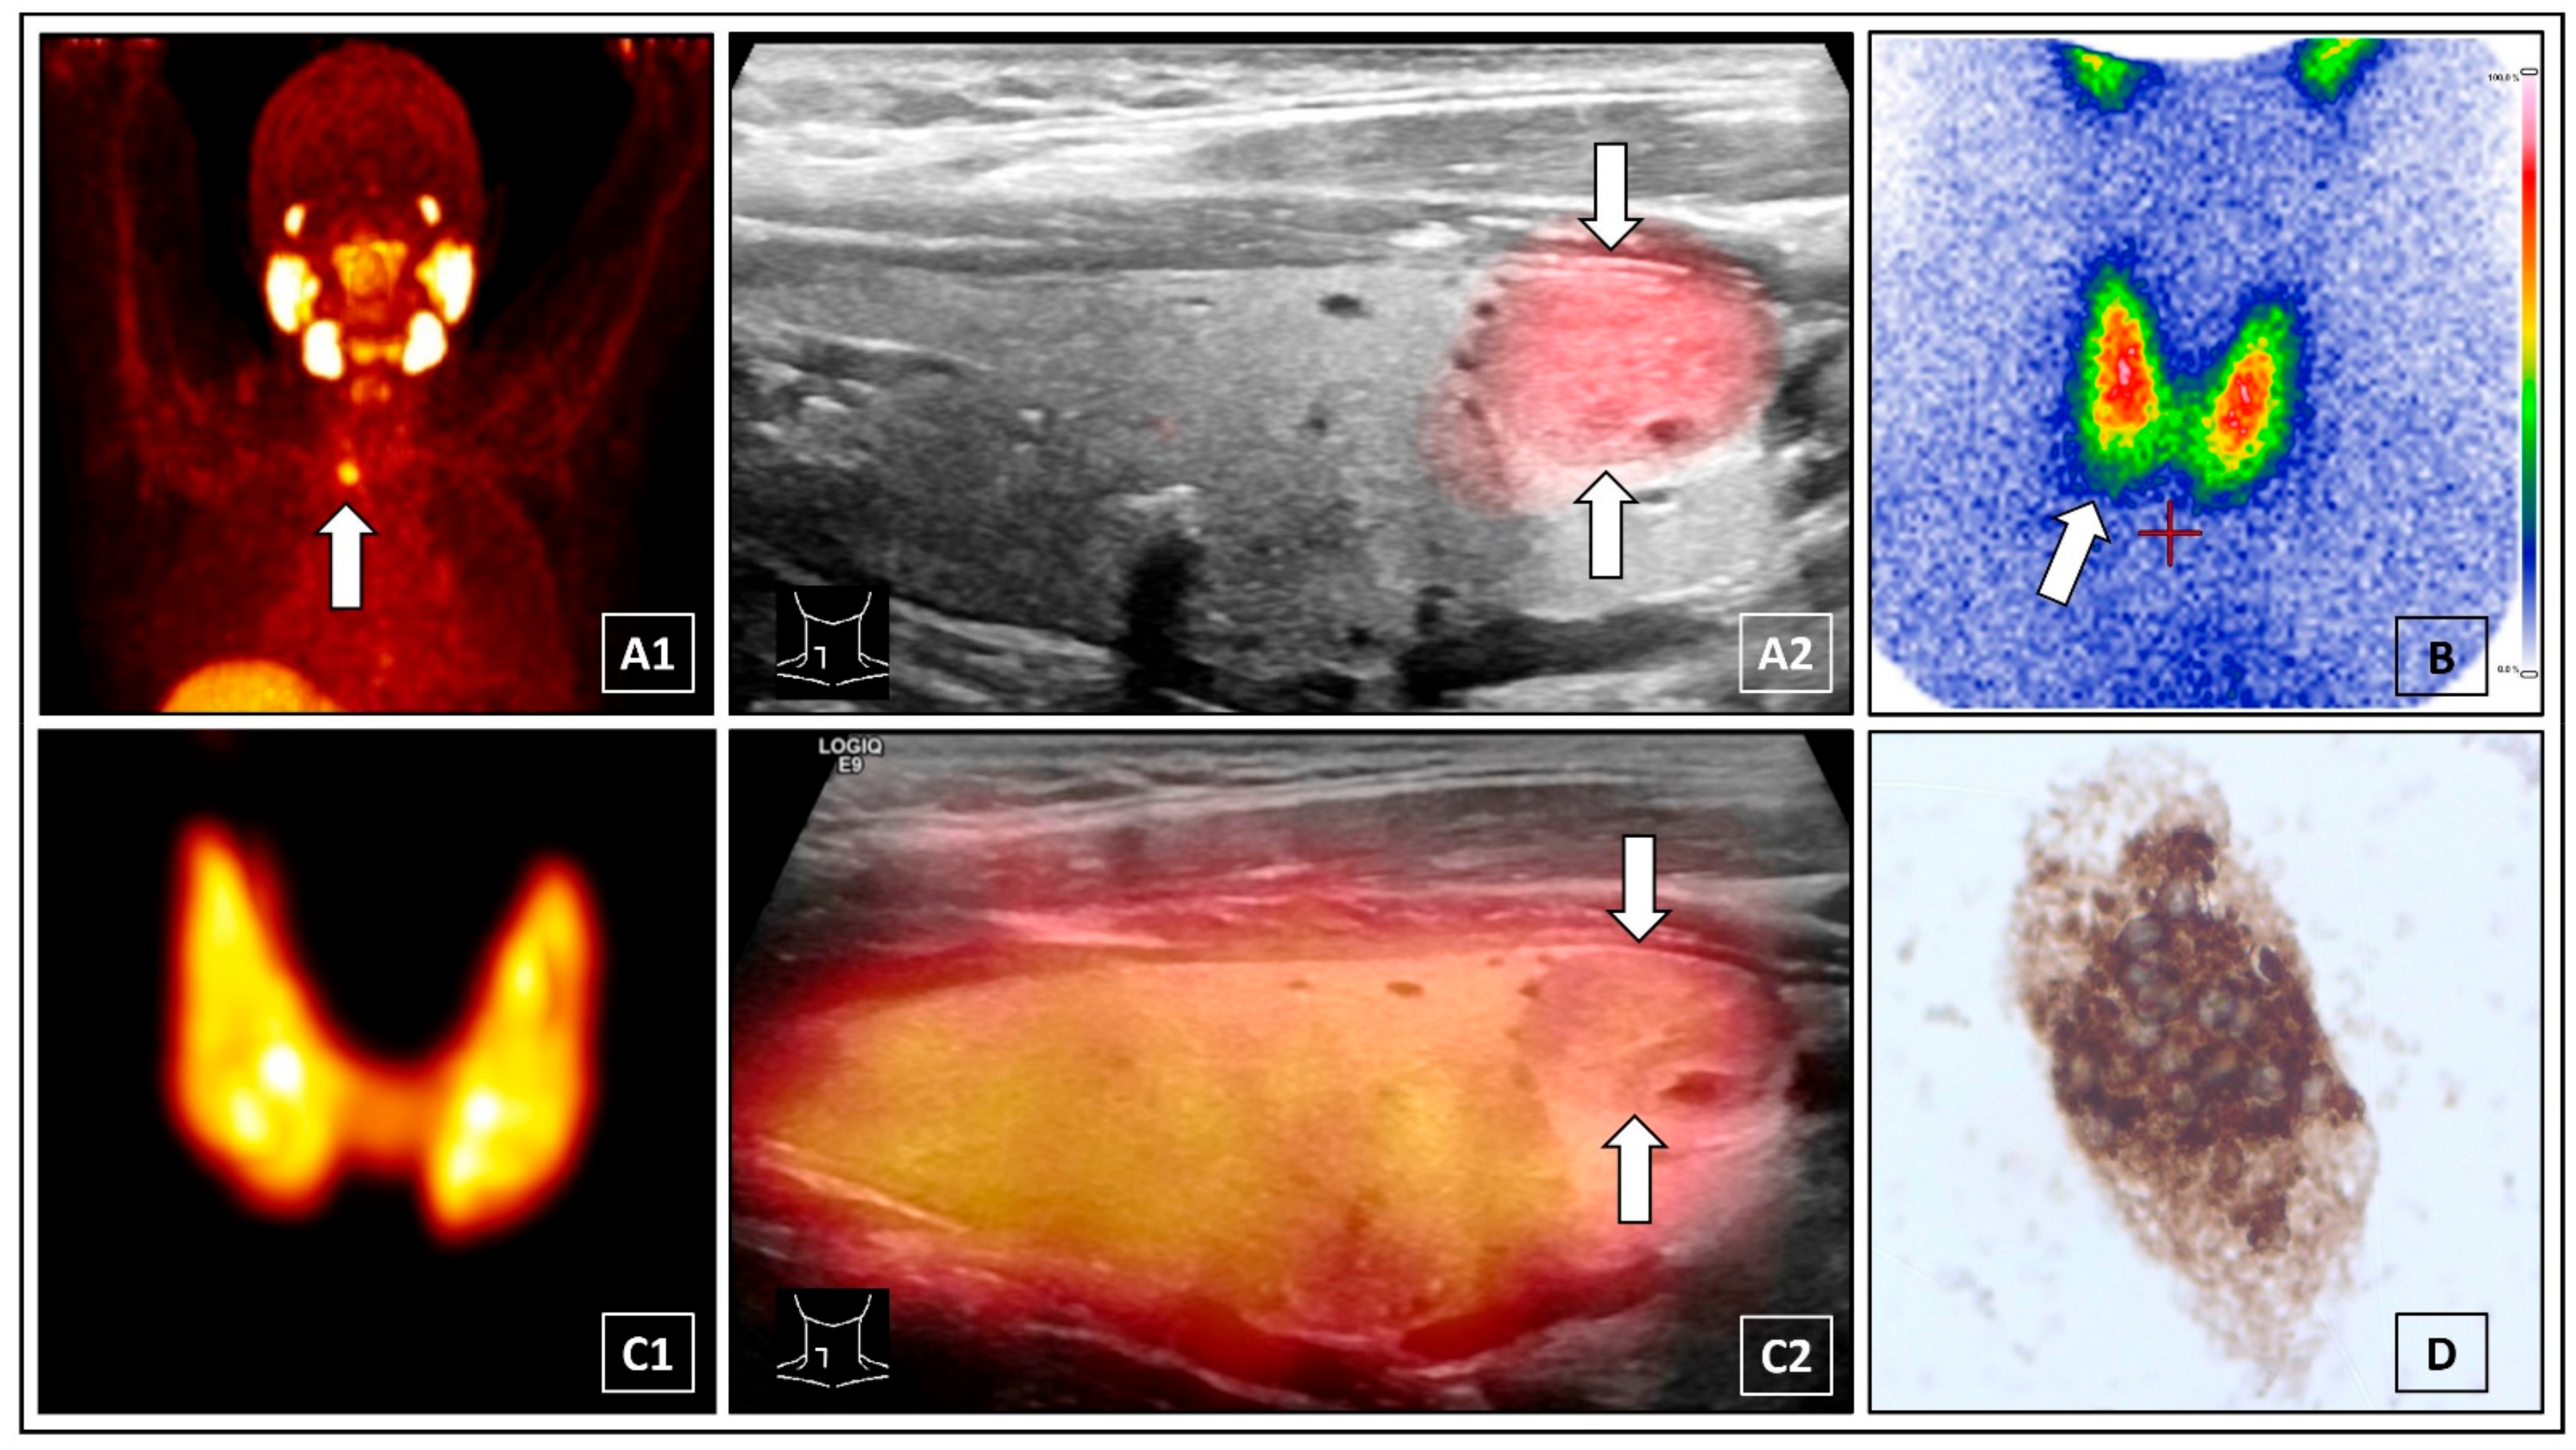

Prostate-specific membrane antigen (PSMA) “theranostics” is gaining increasing importance in the treatment of prostate cancer [1]. A 54-year-old male diagnosed with prostate cancer presented to our clinic for 68Gallium-PSMA-11 PET/CT. The PET-scan incidentally revealed a solitary PSMA-positive lesion of the thyroid gland (A1, white arrow). There was no history of thyroid pathologies and laboratory thyroidal values were normal. Subsequently, 68Gallium-PSMA-11 PET/ultrasound (US) fusion imaging was performed and unambiguously depicted a solitary PSMA-positive thyroid nodule (15 × 13 × 8 mm) in the lower right lobe (A2, white arrows), classified as Kwak-TIRADS 4B [2]. PSMA-positive thyroid uptake can be related to several diagnoses, including thyroid cancer, metastases of prostate cancer or renal cell carcinoma, benign thyroid nodules, and de Quervain’s thyroiditis [3,4,5]. 99mTc-scintigraphy did not clearly characterize the nodule (B, white arrow) and therefore cervical 124Iodine PET/CT was performed. The 124Iodine maximum intensitiy projection (MIP) PET imagiges did not reveal any hyper- or hypofunctional thyroidal lesions (C1). Additional PET/US fusion imaging clearified a normal iodine uptake of the PSMA-positive nodule (C2, white arrows). For real-time PET/US fusion imaging, the PET/CT images (biograph mCT 40; Siemens, Erlangen, Germany) were transferred to the LOGIQ E9 ultrasound device (GE Healthcare, Milwaukee, WI, USA). According to anatomical landmarks on CT, e.g., spine, larynx, trachea, the PET/CT images were manually superimposed and aligned to the ultrasound images using a magnetic field based navigation system and the VNAV software (GE Healthcare) [6]. For 124Iodine PET/US fusion imaging, a single bed position (10 min scan time) low-activity (1 MBq 124Iodine) cervical PET/CT (low-dose CT scan) was performed. The effective whole body dose for the patient was ~6.8 mSv [7]. The “FUSION iENA” study (obtained by independend ratings of 106 nuclear medicine physicians) revealed that 124Iodine PET/US fusion imaging significantly improves the accuracy and the confidence of the functional assessement of thyroid nodules as well as influences the suggested treatment for patients with ambiguous findings on conventional diagnostics [8]. Fine-needle cytology was performed using an magnet-based ultrasound needle-guidance system to ensure that the cells were acquired from the PSMA-positive thyroid nodule [9]. The cytopathological investigation showed a benign thyroid nodule according to Bethesda category II with positive thyroglobulin staining (D) [10]. Finally, thyroid cancer as well as an intra-thyroid prostate cancer metastasis could be ruled out. This interesting image demonstrates the first application of PET/US fusion imaging in a PSMA-positive thyroid nodule and demonstrates the diagnostic potential of combined modern multimodal methods in the field of nuclear medicine.